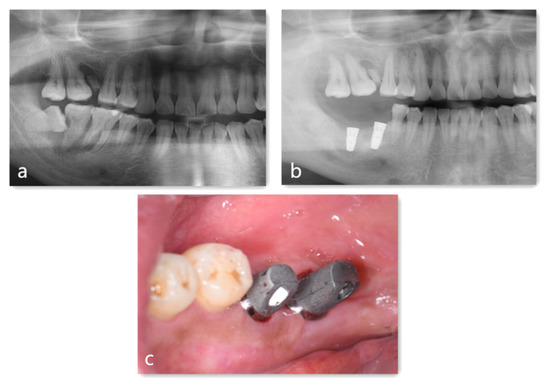

4. Case Report